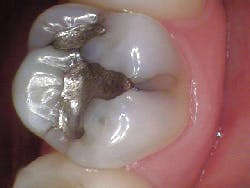

- Fractured cusp (figure 3)

- Cracked tooth (figure 4)